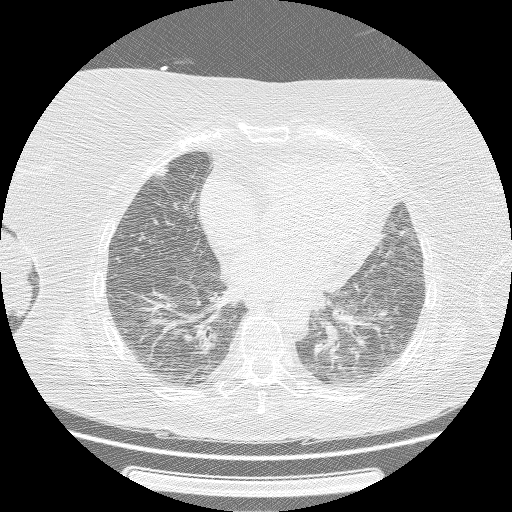

【EIRL Chest CTによる表示例】

② 低線量CT

- 低線量CTについて

- 通常のCTに比べ、被検査者に与える被ばく量を軽減することが可能です。一方、撮影される画像は、通常のCTに比べて質が低下する傾向にあり、読影診断の難易度が高まると言われています。